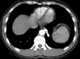

Bronchial atresia